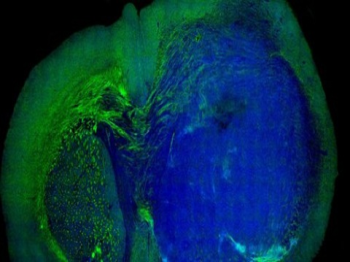

Phẫu thuật bằng tia laser phát hiện bệnh ung thư não

Tạo ra não người nhân tạo

Áo: Phát triển bộ não của con người từ tế bào gốc